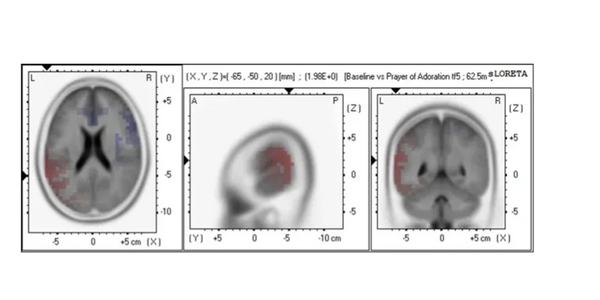

The main effect between the two conditions, Baseline (Not Praying) vs Prayer of Adoration was significant t(44) = 1.98, p = .02699, suggesting that when Christians focused on praising God, there was elevated alpha current source density (CSD) in the temporal lobe (BA 22) brain region. sLORETA SnPM imaging results are presented.